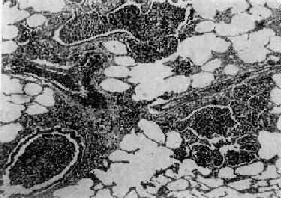

图9-20 间质性肺炎

肺泡壁及细支气管周围肺间质内有大量炎性细胞(主为单核细胞)浸润。肺泡壁明显增宽。肺泡腔内无渗出物